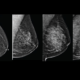

Alguns nódulos podem ser identificados pela mamografia apesar de não serem palpáveis. Nesses casos, o especialista tem necessidade do auxílio de imagens e, em outros, de um guia para chegar até a lesão no momento da cirurgia. A cirurgia de lesão não palpável é guiada através de um marcador para que o médico consiga identificar o local sem afetar a saúde da mama no momento da cirurgia.

As técnicas mais usadas são agulhamento e o Radioguided Occult Lesion Localization (Roll, ou seja, Localização Radioguiada de Lesão Oculta), que são responsáveis por facilitar e tornar a cirurgia o menos invasiva possível. Cada profissional tem a sua técnica preferida, apesar de estudos clínicos comprovarem que as duas formas são semelhantes e alcançam o mesmo resultado.